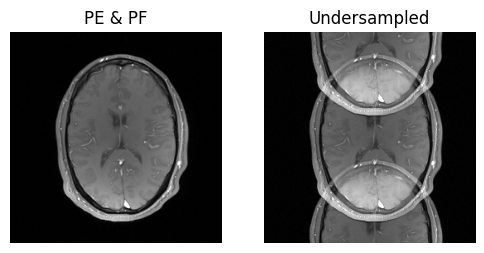

show_images(idat_pe_pf.rss().squeeze(), idat_us.rss().squeeze(), titles=['PE & PF', 'Undersampled'])

../_images/aab494e1bd54f7d856a367ef804f496412e3950e9f6d1936fac060ffe0430add.png